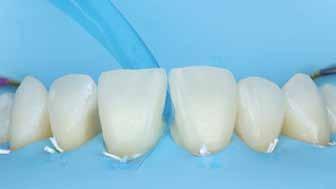

A cikkünkben bemutatásra kerülő eset ellátása során preparációt héjak készre vitele során a platinafólia technikát alkalmaztuk.

kívül vékonyak, és ezáltal a végleges rögzítésük előtt jelentős olyan minimál invazív kezelési eljárásnak számítanak, amely

elérni. A fent leírtak alapján bátran

preparációt nem igénylő héjak készítése mellett döntöttünk. A alkalmaztuk. Annak ellenére, hogy az elkészítésre kerülő héjak rendjelentős törésveszéllyel állunk szemben, összességében mégis amely segítségével kifogástalan esztétikai eredményeket lehet javasoljuk e módszer alkalmazását.